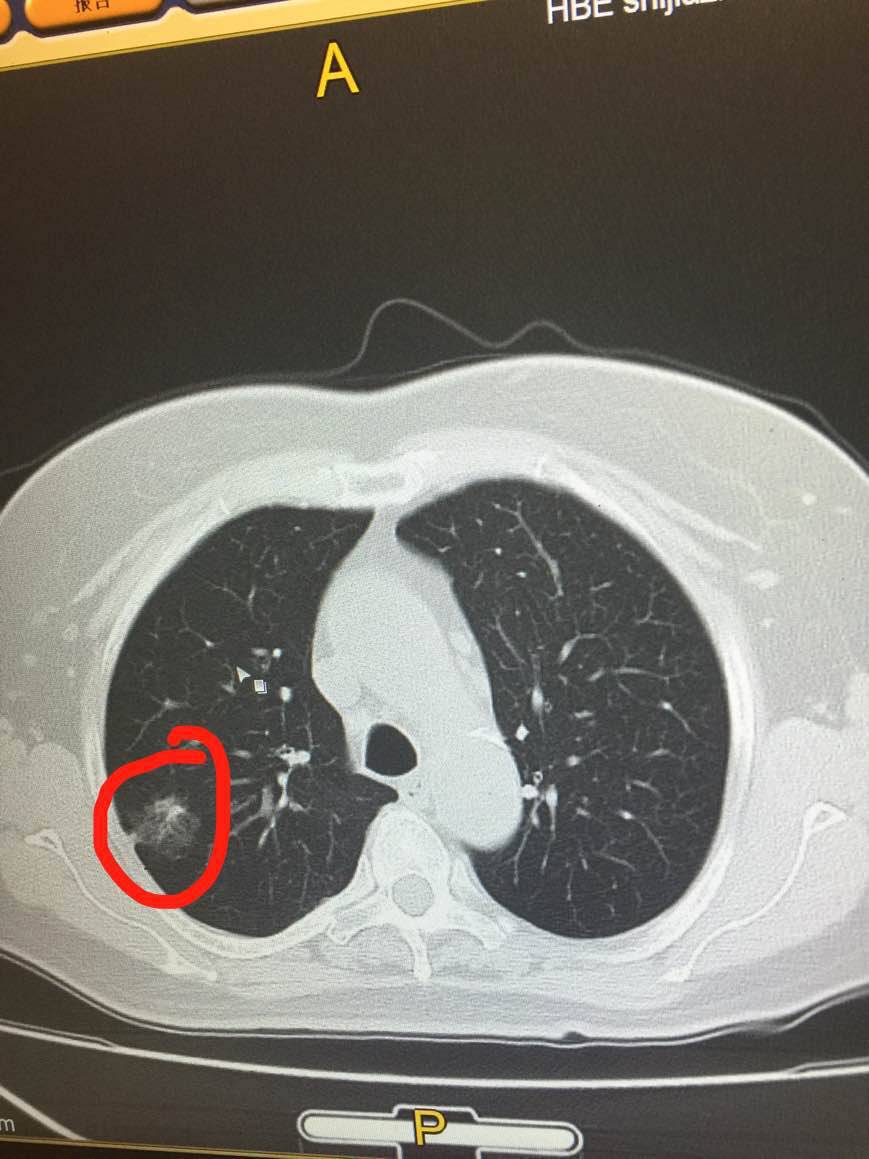

陈医生,这是我母亲的CT,您看一下手机

@陈医生,这是我母亲的CT,花开未全月半弯的CT直接就确诊了吗?

很好,做的很好,看到了